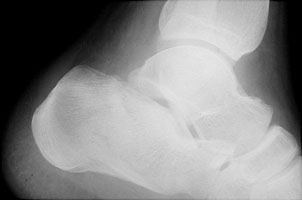

- Click on the image for a larger versionBLateral radiograph of the ankle. This shows flattening of Boehler's angle and sclerosis through the calcaneus.